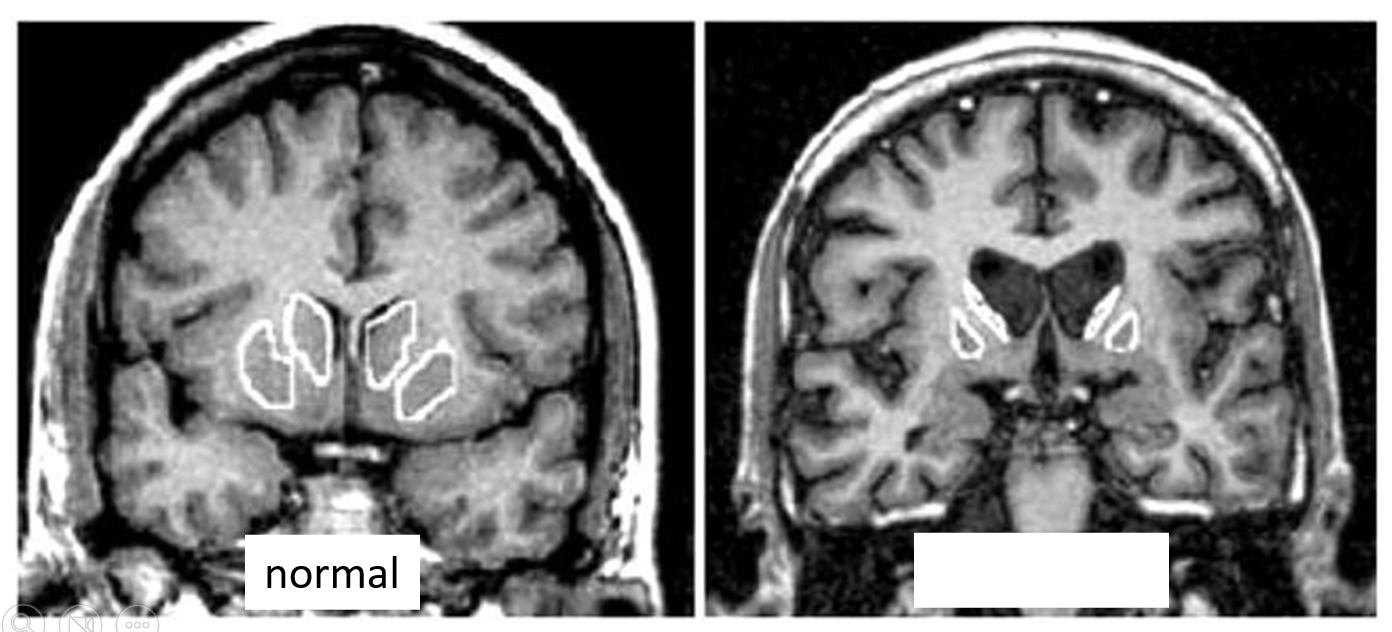

name the condition

Huntington’s (reduced caudate)